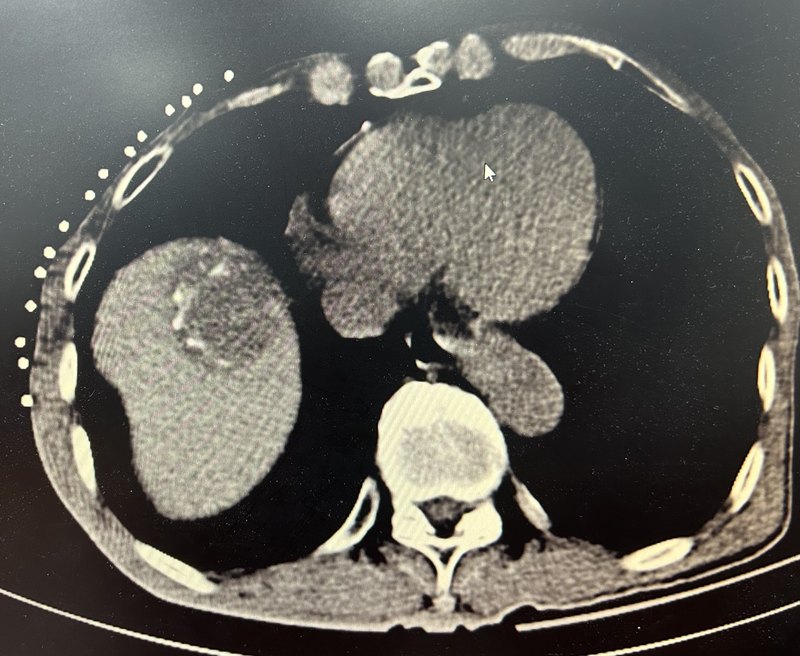

患者老年男性,乙肝肝硬化脾亢門脈高壓多年,近期發(fā)現(xiàn)肝癌。ct可見右肝癌并門脈高壓。造影右肝可見腫瘤染色,脾動脈稍增粗。行tace及脾動脈主干彈簧圈栓塞后再次造影右肝腫瘤未見染色,脾動脈遠端血流減少。行脾微波消融糾正脾亢。行肝癌微波消融治療。右肝腫瘤完全滅活,脾臟可見片狀壞死灶,脾臟明顯縮小。再次造影右肝腫瘤未見染色,脾動脈中段部分閉塞,脾臟血流減少。點評:對于小肝癌合并門脈高壓脾功能亢進,我們推薦采取脾動脈主干彈簧圈栓塞限流降低門脈壓力,聯(lián)合內鏡下套扎避免消化道出血,然后行脾微波消融糾正脾功能亢進,同時tace聯(lián)合微波消融滅活肝腫瘤的方案,同時治療肝癌及門脈高壓,相信這個方案未來會被主流接納成為首選方案。